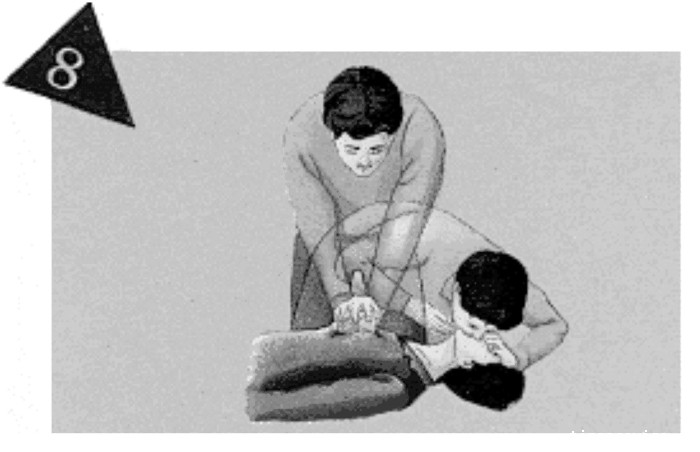

进行胸外按压与人工呼吸:

先连续15次按压后,接着2次人工呼吸。

·胸外心脏按压应与人工呼吸同步进行。先做2次人工呼吸,再做15次按压,如此类推。